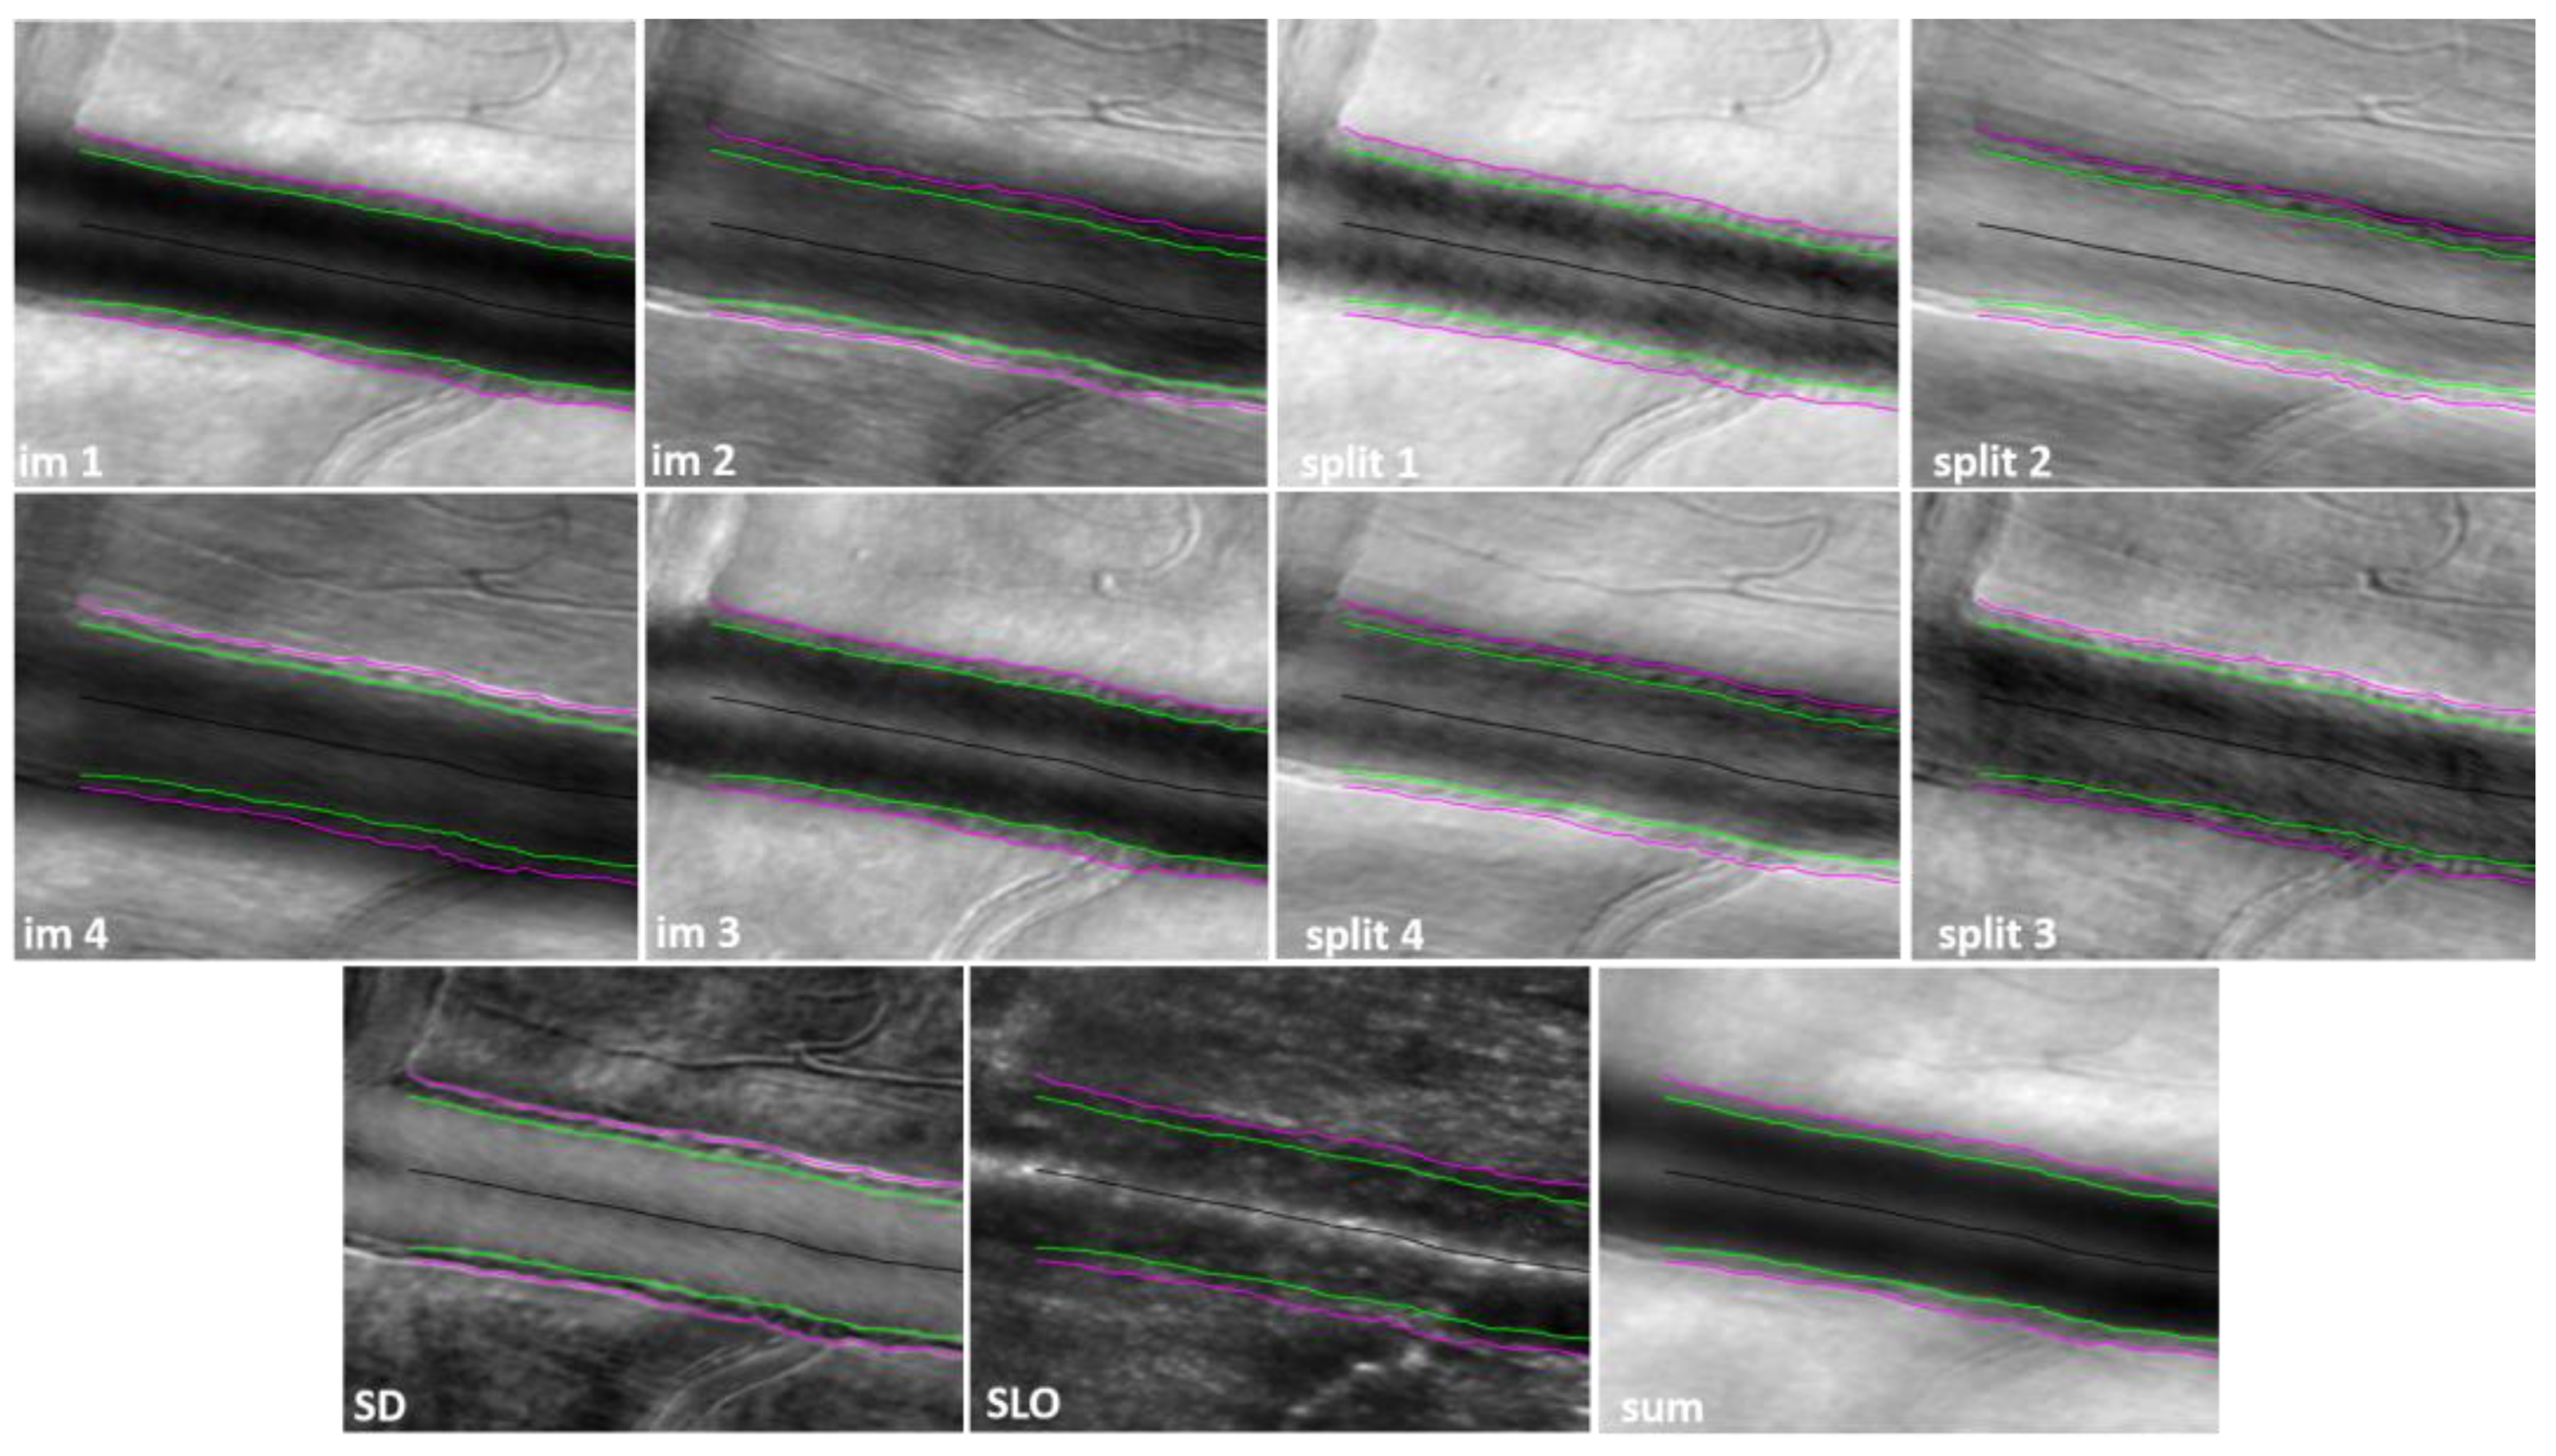

2. Materials and Methods

2.3. Confocal and Non-Confocal Imaging

3. Results

4. Discussion